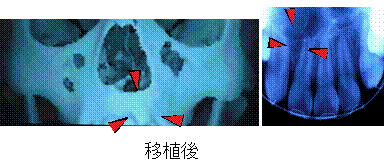

乳幼児期に口唇裂及び口蓋裂の手術を行うと、裂隙は粘膜で覆われ外から見ると裂は無くなったようにみえますが、上顎の骨の裂隙(顎裂)は残っています。顎裂があると、歯を隙間なく並べることができません。そのためこの部分に骨を埋める手術が必要となります。

当センターでは、8~10歳頃に、腸骨(腰骨)から海綿状の骨片を採取して、顎裂部に埋めるようにしています。適切な時期に手術を行えば、永久歯の犬歯を骨移植した部位に萌出させることができます。